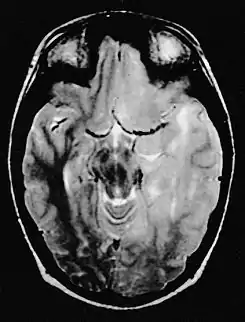

En las imágenes de resonancia magnética, el tumor aparece como una lesión difusa, poco circunscrita, infiltrante y sin captación de contraste, con señal hiperintensa en las imágenes ponderadas en T2, y que se expande hacia la materia blanca. Puede ser difícil de distinguir de un astrocitoma anaplásico altamente infiltrante o un glioblastoma.[6]

Es típica la afectación de los dos hemisferios cerebrales. También puede afectar al tronco cerebral, el cerebelo y la médula espinal.

La característica radiológica más frecuente en la RM es la infiltración en forma de lesión hiperintensa en T2 y FLAIR tanto de la sustancia blanca como de la sustancia gris. Con la administración de contraste el realce es mínimo o ausente.[14][15]